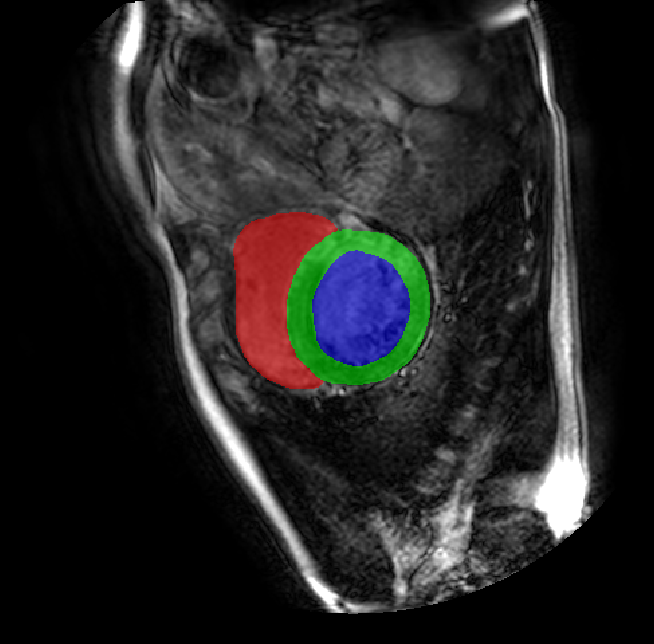

Table 2 presents an ablation study and compares SparseMamba-PCL with nine SOTA scribble-supervised methods across the three datasets. Out method achieves the highest Dice score across all the datasets, and the lowest (CHAOS) and second lowest (ACDC and MSCMRSeg) HD95 values, confirming its effectiveness in segmentation accuracy and boundary refinement. Baseline+SPOBE and Baseline+PCL improve upon the Baseline (SparseMamba), demonstrating the benefits of boundary-aware supervision and SAM-guided learning. Fig. 4 (l) compares the segmentation performance of SparseMamba-PCL with other scribble-supervised methods, showing smoother edges that precisely delineate object boundaries, unlike the jagged or blurred edges in other methods. The examples also demonstrate the consistent segmentation quality achieved by SparseMamba-PCL across ACDC, CHAOS, and MSCMRSeg, highlighting its adaptability across multiple medical domains. This adaptability and precise segmentation is crucial for accurate volumetric analysis and clinical decision-making, where even subtle boundary inaccuracies can lead to diagnostic errors. In summary, the SparseMamba-PCL architecture provides a consistent and robust improvement in segmentation metrics across diverse medical image datasets.

Refer to caption Refer to caption Refer to caption Refer to caption Refer to caption Refer to caption Refer to caption Refer to caption Refer to caption Refer to caption Refer to caption Refer to caption

(a) (b) (c) (d) (e) (f) (g) (h) (i) (j) (k) (l)

Figure 4: Qualitative comparison of weakly-supervised segmentation methods on ACDC, CHAOS, and MSCMRSeg datasets. (a) Input image, (b) ground truth, and segmentation results from (c) USTM [16], (d) Scribble2D5 [5], (e) CycleMix [26], (f) ShapePU [27], (g) S²ME [21], (h) ScribbleVC [12], (i) TDNet [30], (j) PacingPseudo [25], (k) Scribbleformer [13], and (l) SparseMamba-PCL are given.